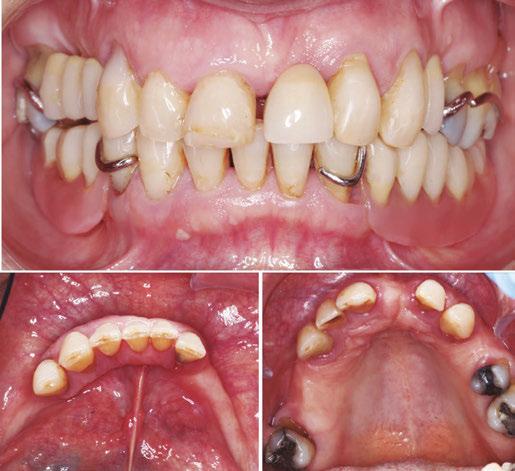

Protocolo Di2gitalArch® 2.0: Carga inmediata en el día en maxilar superior atrófico. Con Ziacom Galaxy, por el Dr. Luis Cuadrado Canals.